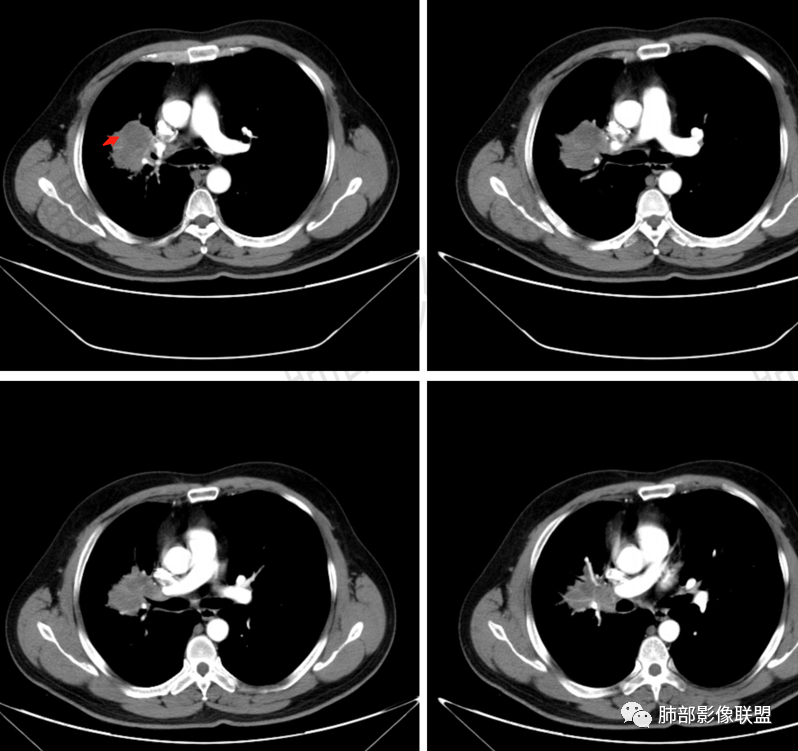

Coke with ice:病变整体收缩平直,毛刺较软,支气管壁增厚。支气管鼠尾状狭窄,于病灶以远可见显示。支气管粘液栓。相邻支气管血管推移明显,磨玻璃边缘模糊,多灶坏死边缘清晰,一部分血管自然穿行,猜个炎性病变。

这个比较大的坏死灶,边缘清晰,看似符合鳞癌坏死。仔细看看这个坏死边界,是血管阻挡引起的边界清晰。其他的病灶内低密度是柱形粘液栓。实性部分强化有轻度延迟强化。病变背景是双上肺的小叶中心结节。病变区的支气管壁是厚的。

妞妞:右肺门区病灶,边缘有GGO,模糊,远端树芽,支气管受阻,有圆钝感,病灶坏死,边缘清楚,实性成分有强化,不像鳞癌强化,首先考虑结核,鳞癌待排,建议支气管镜

良孑:右肺门肿块,有平直,u型凹陷及尖角征,远端可见散发树芽征,有支气管截断,肿块内坏死边界清,似可见围绕坏死的环状强化,综合分析首选炎性病变,TB可能,冇吸烟史,良恶性征象都有鳞癌要鉴别,

前段支气管鼠尾状狭窄,壁增厚

尖段/后段支气管受压推移

远端有些花花草草

总觉得有部分指套改变